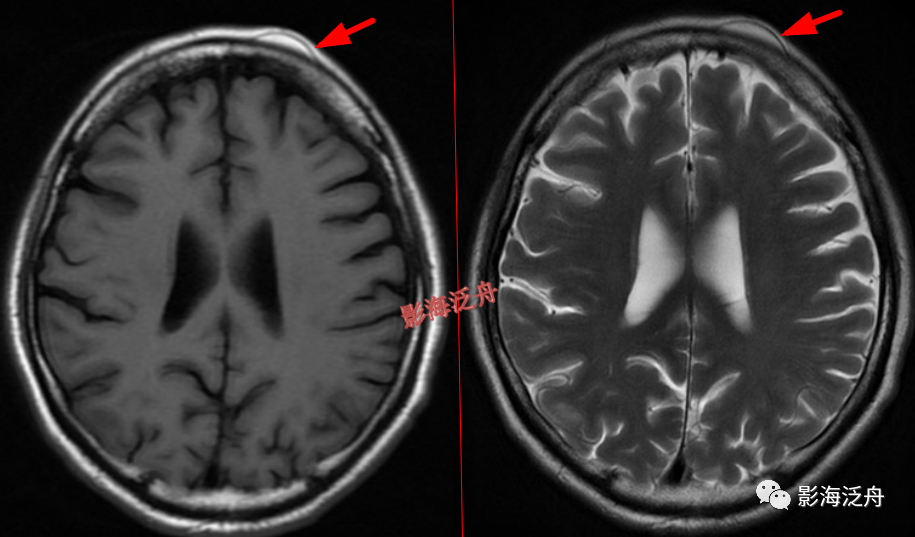

头皮下病变

头皮下血管瘤以及皮脂腺瘤是非常常见的,单也很容易漏诊,尽管临床意义不大,但还是应当避免漏诊,毕竟现在的大家的处境一言难尽~

右侧额部头皮下血管瘤。患者为11岁女性,是本病的高发年龄段,这个结节要是漏诊,恐怕会有麻烦。